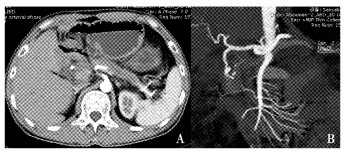

结果  6例假性动脉瘤中3例位于脾动脉, 另3例分别位于胃十二指肠动脉、胃网膜右动脉和胰十二指肠下动脉。增强CT发现4例, 全部通过数字减影血管造影(digital subtraction angiography, DSA)明确诊断并采取经导管动脉栓塞治疗, 技术成功率和临床成功率达100%, 无严重并发症发生。

Results  The locations of these 6 pseudoaneurysms included splenic artery (n=3), gastroduodenal artery (n=1), right gastroepiploic artery (n=1), and inferior pancreatioduodenal artery (n=1). Four pseudoaneurysms were detected by contrast-enhanced computed tomography (CT) and all were showed in digital subtraction angiography (DSA). TAE was performed as the first-choice management and the hemorrhage was controlled in all cases. Both the technical and clinical success rates reached 100% and no major complications occurred.